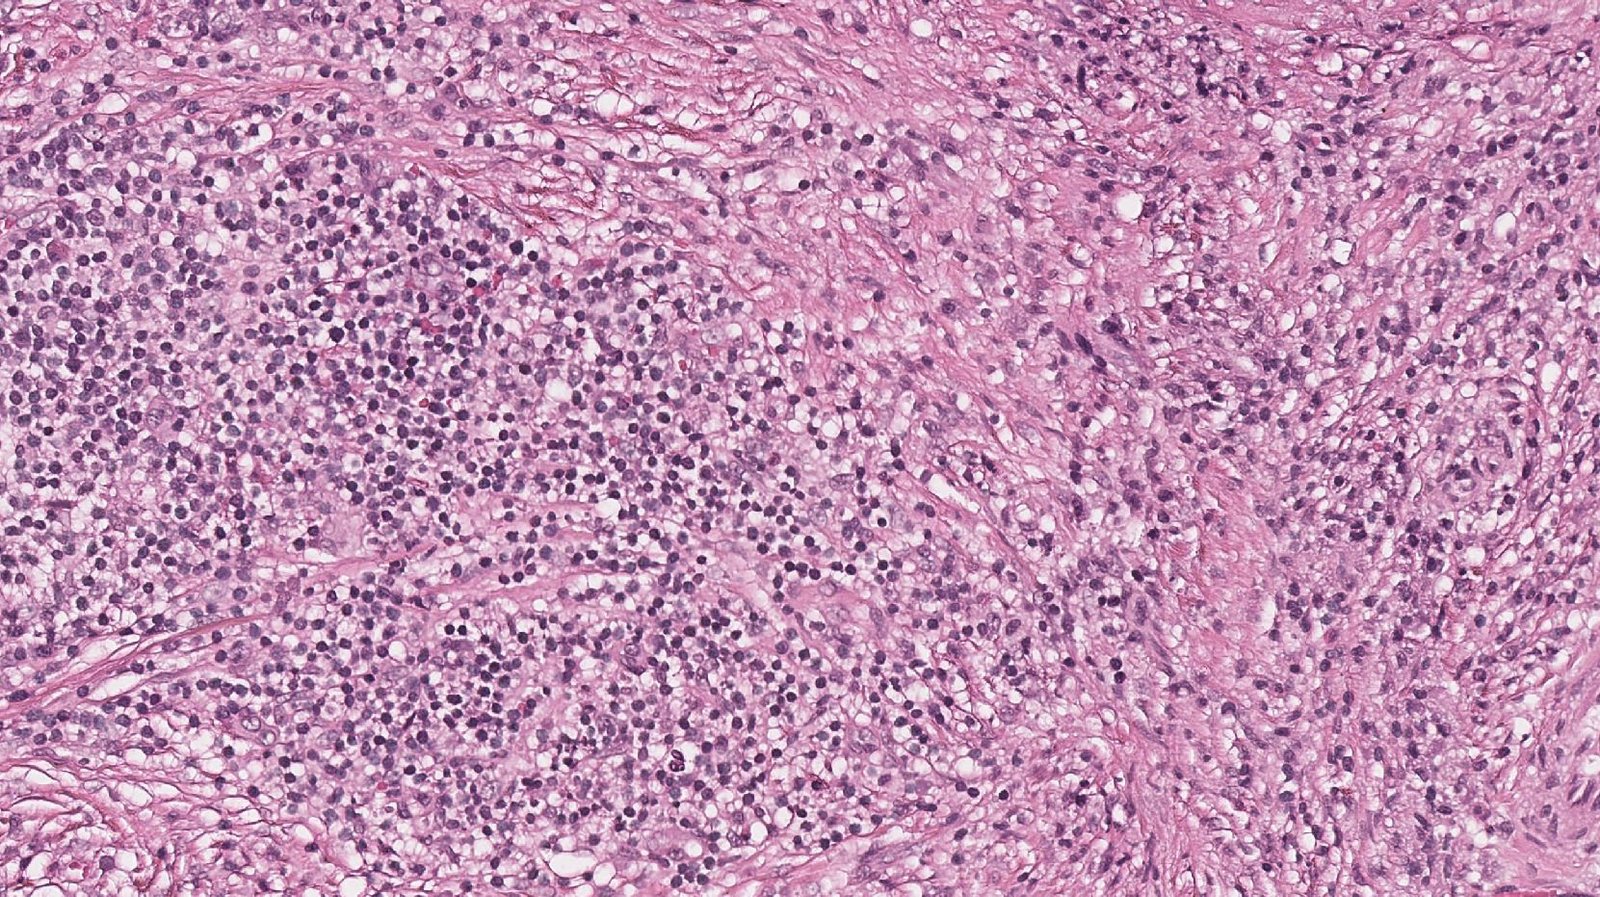

Case: LungMass

Specials to Order:

Final Diagnosis: